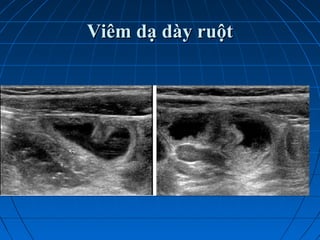

Viêm dạ dày ruột và viêm đoạnViêm dạ dày ruột và viêm đoạn

cuối hồi tràngcuối hồi tràng

 Triệu chứng lâm sàng rầm rộ , triệuTriệu chứng lâm sàng rầm rộ , triệu

chứng siêu âm nghèo nànchứng siêu âm nghèo nàn

 Trong các trường hợp điển hìnhTrong các trường hợp điển hình

thường không cần đến siêu âmthường không cần đến siêu âm

 Trường hợp không điển hình (hộiTrường hợp không điển hình (hội

chứng ruột thừa, bệnh cảnh giốngchứng ruột thừa, bệnh cảnh giống

lồng ruột…) siêu âm có vai trò quyếtlồng ruột…) siêu âm có vai trò quyết

định chẩn đoánđịnh chẩn đoán

 Viêm dạ dày ruột:Viêm dạ dày ruột:

Ruột non ứ dịch , tăng nhu động ,Ruột non ứ dịch , tăng nhu động ,

thành không phù nề hoặc phù nềthành không phù nề hoặc phù nề

nhẹ, hạch mạc treo dạng viêm,nhẹ, hạch mạc treo dạng viêm,

không kèm bất thường nào kháckhông kèm bất thường nào khác

 Viêm đoạn cuối hồi tràng:Viêm đoạn cuối hồi tràng:

Hồi manh tràng viêm phù nề, hạchHồi manh tràng viêm phù nề, hạch

mạc treo,+/- dịch xuất tiết vùng HCPmạc treo,+/- dịch xuất tiết vùng HCP

ruột thừa bình thườngruột thừa bình thường

Viêm dạ dày ruộtViêm dạ dày ruột